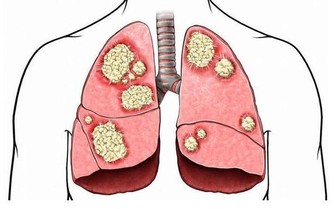

牙結石會不斷刺激牙周組織,並會壓迫牙齦影響血液迴圈,

造成牙周組織的病菌感染,引起牙齦發炎萎縮,形成牙周囊袋。

當牙周囊袋形成後,更易使食物殘渣、牙菌斑和牙結石等堆積,

這種新的堆積又更進一步的破壞更深的牙周膜,

最終會讓牙周組織全部破壞殆盡,而使牙齒難逃拔除的惡運。